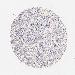

MUC1 is not prognostic in Kidney Renal Clear Cell Carcinoma (validation)

Best expression cut offi

Based on the FPKM value of each gene, patients were classified into two groups and association between prognosis (survival) and gene expression (FPKM) was examined. The best expression cut-off refers the FPKM value that yields maximal difference with regard to survival between the two groups at the lowest log-rank P-value. Best expression cut-off was selected based on survival analysis .

When clicking on this number, the vertical dashed line indicating cut-off, the interactive survival plot, and the Kaplan-Meier curve will be adjusted to show results based on the best expression cut-off.

: 24.39

P scorei

Log-rank P value for Kaplan-Meier plot showing results from analysis of correlation between mRNA expression level and patient survival.

N/A

TCGA RNA samplesi

RNA-seq data is reported as average FPKM (number Fragments Per Kilobase of exon per Million reads), generated by the The Cancer Genome Atlas (TCGA) .

Normal distribution across the dataset is visualized with box plots, shown as median and 25th and 75th percentiles. Points are displayed as outliers if they are above or below 1.5 times the interquartile range. FPKM values of the individual samples are presented next to the box plot.

Average pTPM 95.3

Number of samples 100